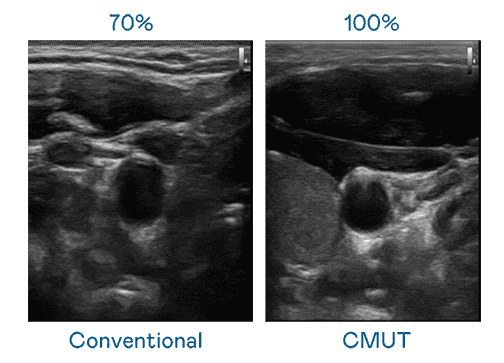

CMUT 技术是一种用电容式微机电元件来产生超音波讯号的技术。。。。与传统 PZT 压电式技术相比,,CMUT 频宽增加 30%,,更宽频的超音波讯号让影像解析度大幅提升,,,是实现高影像品质医疗超音波扫描、、促进精准医疗发展的关键技术。。。

超音波影像的解析度高低,,,,首先取决于探头能发出的讯号频宽。。。。JDB电子 CMUT 可提供高清晰的超音波讯号,,,,提供高频宽、、、、高灵敏度、、、影像纹理细节更高的超音波影像,,,,协助医护人员缩短影像判读时间及利用精准的医疗影像进行诊断。。